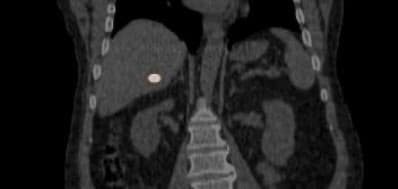

• YntraDose (previously called BAT-90) has been studied in a FIH Trial to assess the performance of BAT-90 during the percutaneous ablative procedure of resectable and unresectable primary liver lesions (HCC).

The study indicated that No treatment related AEs and ADEs limiting the ability to deploy YntraDose occurred and 100% of the lesions treated showed to have been reached by the product.